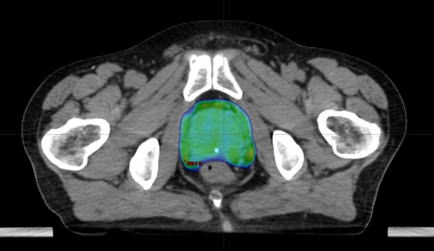

治療計画の様子

前立腺癌に対するVMAT